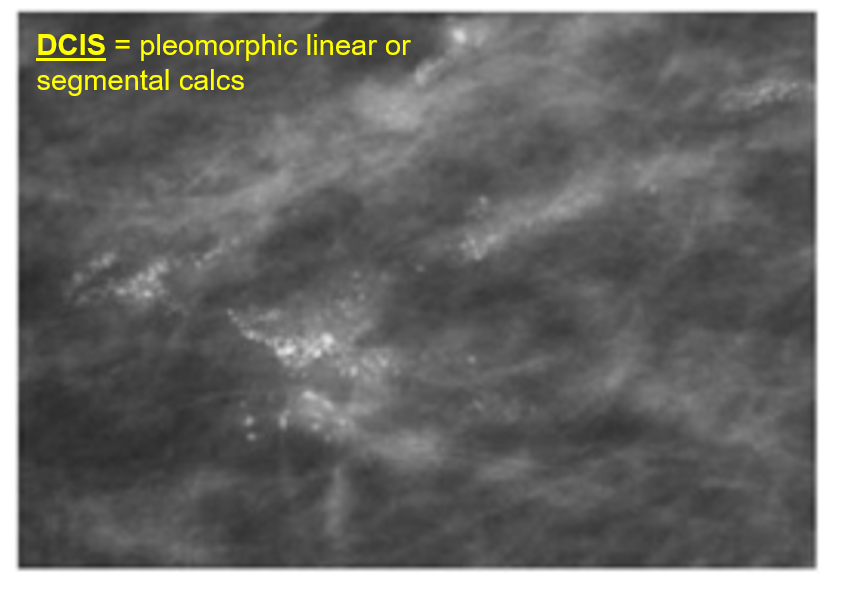

calcifications in DCIS are due to

comedo necrosis in ducts

segmental fine pleomorphic calcs. BAD!

BR 5